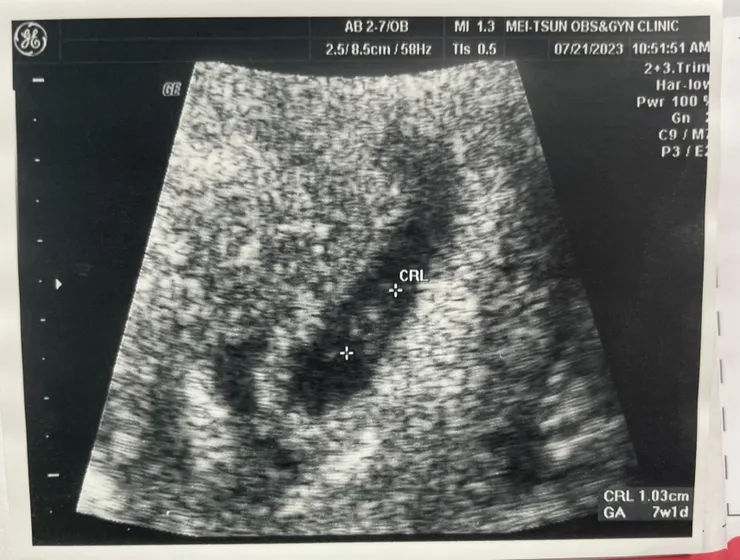

第一張小福氣照片!! 小小的只有1.03cm

兩週後第二次產檢,竟然聽到心跳了,大小是7週1天!!我的心也蹦蹦跳阿!!! 差點噴淚~上週免疫科的抽血報告也正常,但要持續觀察所以又抽了一針!